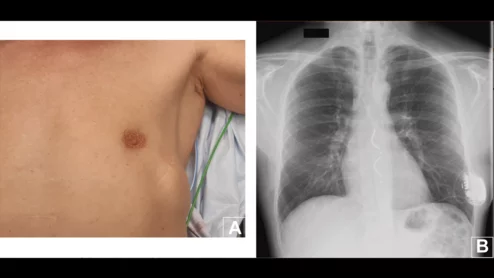

Cardiologists have performed what they believe to be the world’s first substernal lead extraction, sharing their experience in JACC: Case Reports.[1]The device being extracted, Medtronic’s Aurora EV-ICD, received U.S. Food and Drug Administration (FDA) approval in October 2023.

The 49-year-old patient was not in pain or suffering any complications, but he wished to have his extravascular ICD removed once his symptoms improved. The care team agreed to extract it after a long discussion, and they said it was "easier than expected."